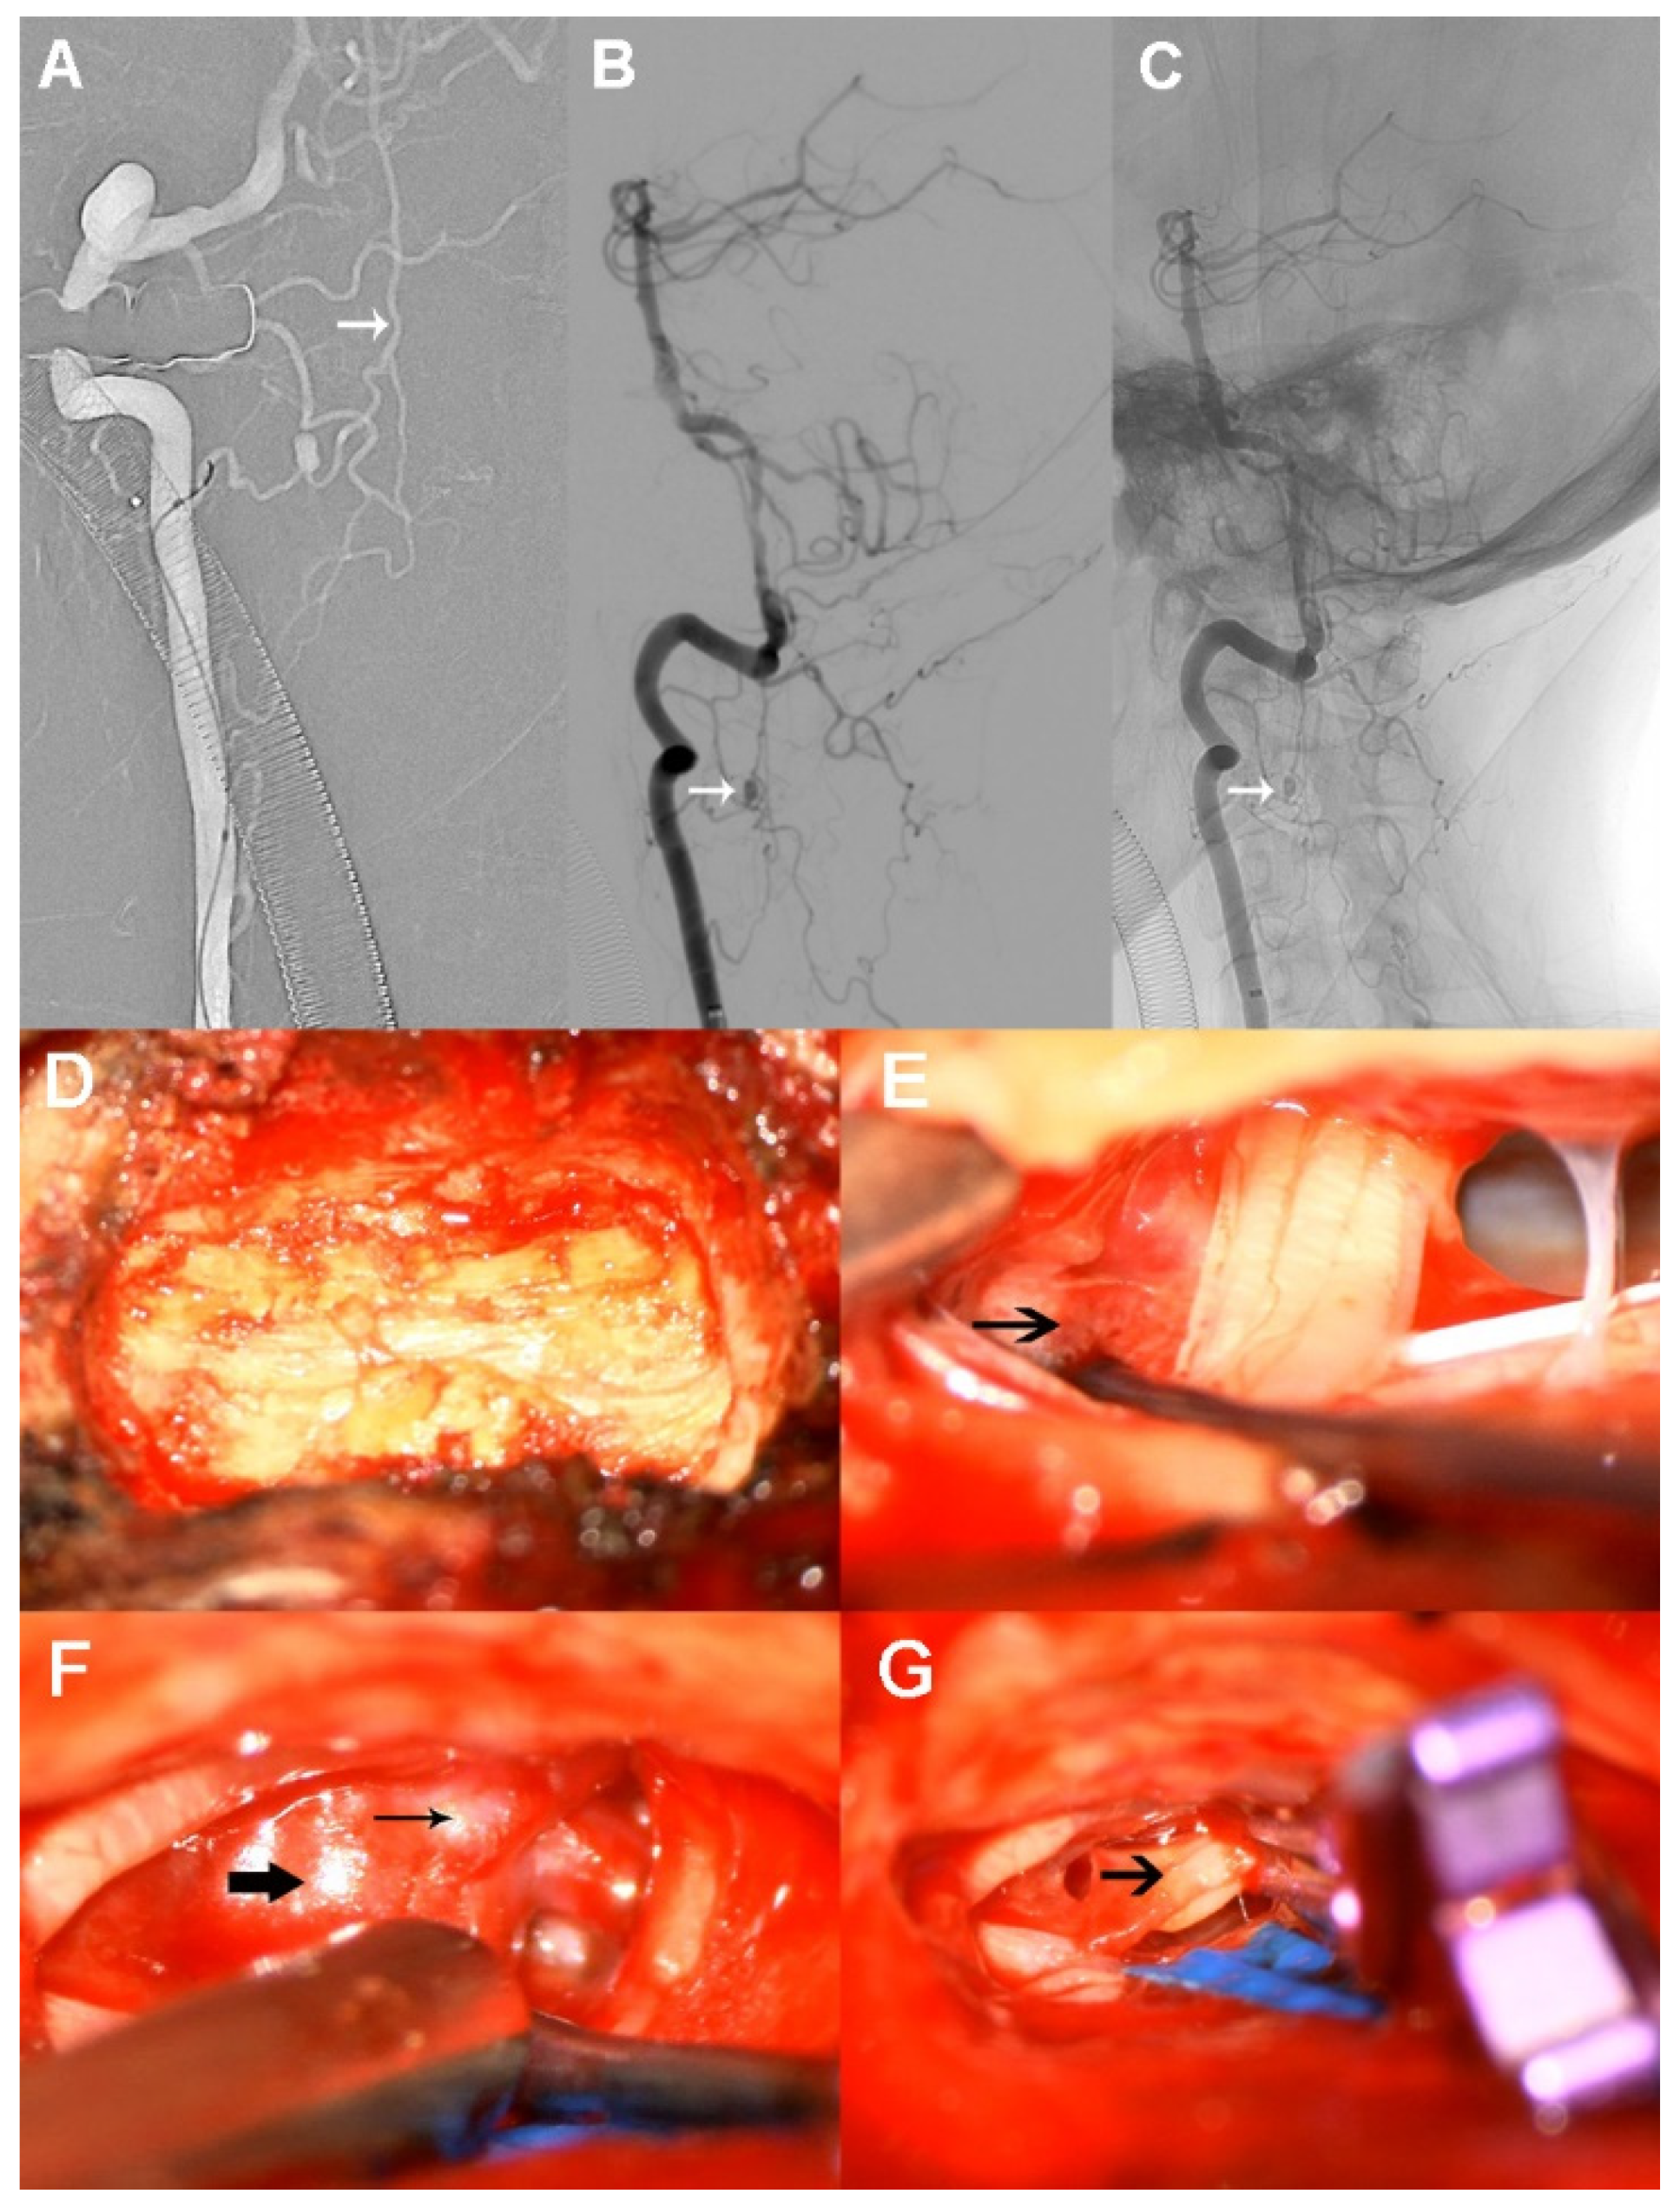

2. Case Presentation